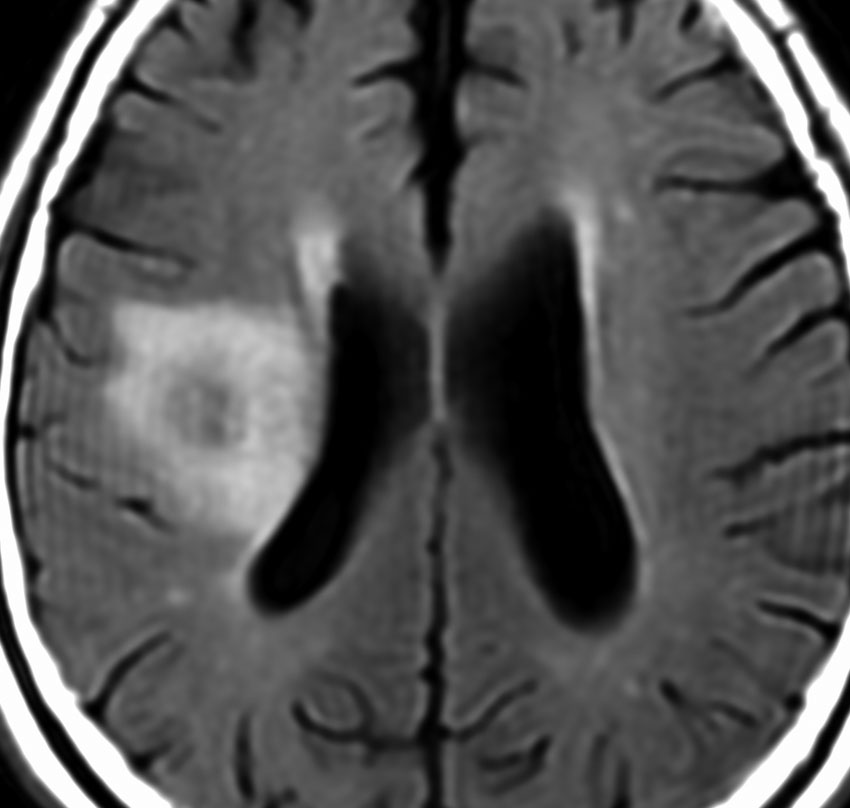

60代の患者さんの右前頭葉深部から島回に発生したものです。初発症状は症候性てんかんです。

ガドリニウム増強される腫瘍の中心部に壊死があり,悪性神経膠腫としては腫瘍周囲浮腫が強すぎるように見えるので,リンパ腫 PCNSLに似た画像所見です。

脱髄性疾患であるtumefactive multiple sclerosisに画像所見も病理所見も類似することがあります。